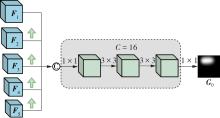

乳腺癌是全球女性最常见的恶性肿瘤之一,准确的病变分割对于乳腺癌的早期诊断与治疗具有重要意义。然而,由于病变形态的多样性以及超声成像机制的复杂性,现有基于深度学习的乳腺超声图像病变分割方法在分割准确性方面仍面临巨大挑战。为进一步提升乳腺超声图像中病变区域的分割精度,该文基于经典U-Net架构,提出了一种新型乳腺超声图像病变分割网络(CWSASKM-BBAM-Net)。首先,在网络中引入逐通道空间自适应选择核卷积模块(CWSASKM),根据不同通道的语义特征为每个空间位置自适应选择感受野大小,以增强多尺度信息的建模能力;然后,引入双向边界感知机制(BBAM),通过融合正向与反向注意力,对目标显著区域及其边界进行协同建模,同时逐步提升对非显著区域与病变区域的区分能力,以进一步强化边界信息的表达;最后,在3组公开乳腺超声图像数据集(BUSI、UDIAT和STU)上开展分割实验。结果表明:该方法在数据集BUSI上的杰卡德指数、精确率、召回率和Dice相似系数分别为71.97%、82.85%、81.40%和80.44%,较次优方法分别提升1.69、1.05、1.28和1.84个百分点;在数据集UDIAT上,这4项指标分别达到78.14%、88.31%、86.73%和86.10%,较次优方法分别提升了2.75、2.04、0.56和2.01个百分点;在外部数据集STU上,该方法也取得了优于其他方法的整体表现。实验结果表明,CWSASKM-BBAM-Net在乳腺超声图像分割任务中展现出更优的整体性能。